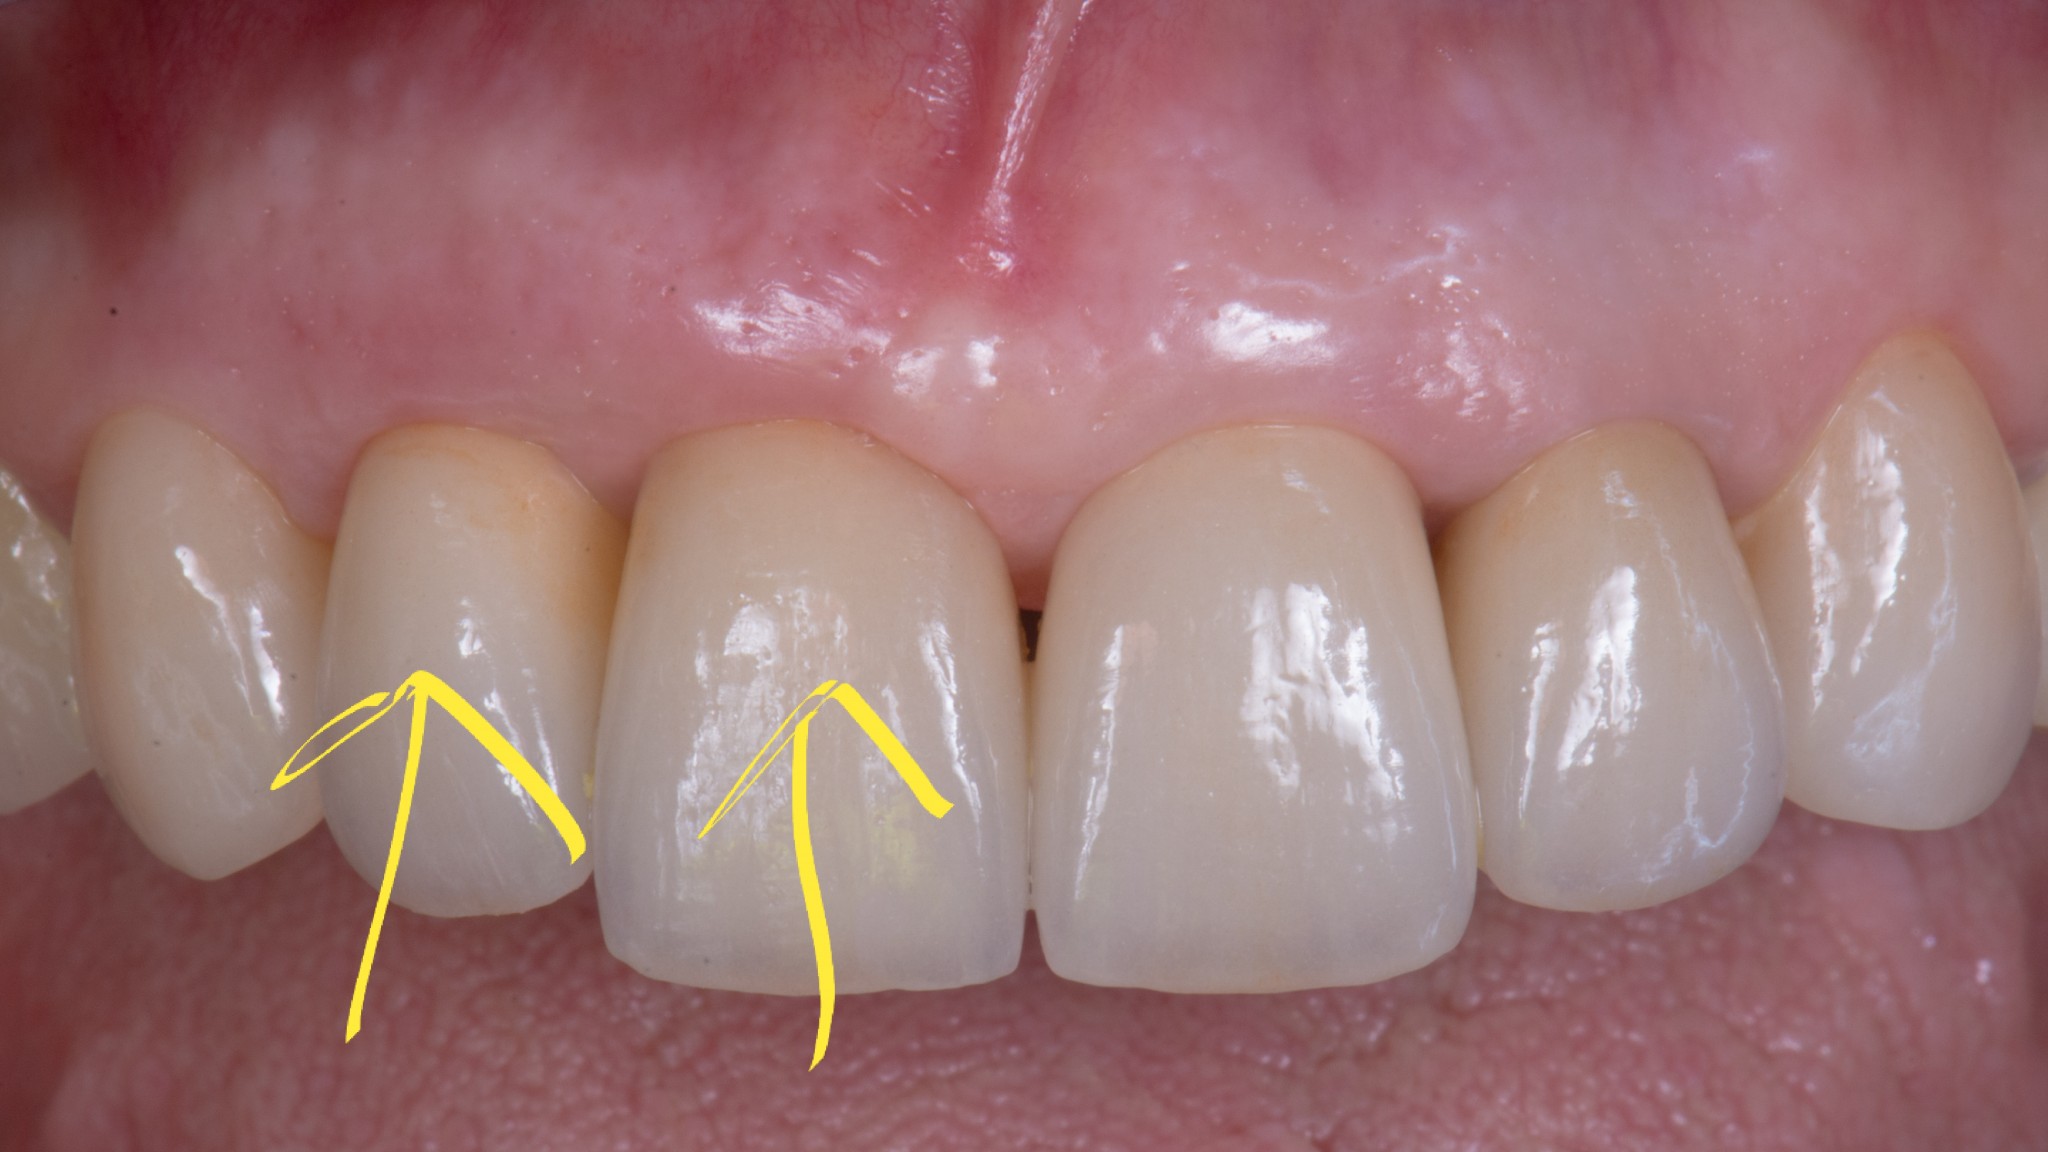

corso gestione tessuti molli - guarigione 1

corso gestione dei tessuti molli - guarigione 2

Ti mostro la foto a sette giorni per due motivi.

• La bellezza di una chirurgia si valuta dalla guarigione a sette giorni. Se aspetti 2 anni, alla fine anche una chirurgia di merda guarisce.

• Ho operato la paziente 7 giorni fa e non ho foto più recenti ma penso che concorderai con me che dopo una guarigione così difficilmente avremo delle sorprese.

Come puoi vedere abbiamo risolto completamente il deficit dei tessuti molli che era stato lasciato dopo le precedenti terapie e…

… posto le basi per una nuova riabilitazione definitiva che si possa definire esteticamente degna dei tempi in cui abbiamo la fortuna di vivere.